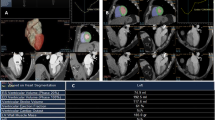

During a single breath hold (lasting 5 s or less), single heartbeat ECG-gated 320-slice volume cardiac CT (Aquilion ONE, Toshiba Medical Systems, Otawara, Japan) was performed with the following volume scanning parameters: 100 kVp, 250 mA, collimation 0.5 mm, rotation time 0.35 s, range 160 mm, field-of-view 320 mm. Automatic tube current monitoring technology was used to reduce the radiation exposure and ensure the image quality. No β-blocker preparation was used. All patients had a regular ventricular rhythm during the examination. Contrast injection was done using 45 ml nonionic contrast agent (Omnipaque 350 mgI/ml, GE, USA) at a flow rate of 4.5 ml/s, followed by 45 ml saline at the same flow rate. From early systole to late diastole (0–95 % R–R interval), volume data from 20 phases were reconstructed at 5 % intervals with slice thickness of 0.5 mm. The RV volume was defined from RV apex to tricuspid valve level. The RV outflow tract to the pulmonary valve was included. Semi-automatic contour detection of the RV was performed, as well as manual correction if necessary. RV function-related parameters including right ventricular end-diastolic volume (RVEDV), right ventricular end- systolic volume (RVESV), right ventricular stroke volume (RVSV), right ventricular cardiac output (RVCO), and right ventricular ejection fraction (RVEF) were calculated using Cardiac Function Analysis (CFA) software in VITAL-fx workstation (Toshiba, Japan) (Figs. 1, 2).